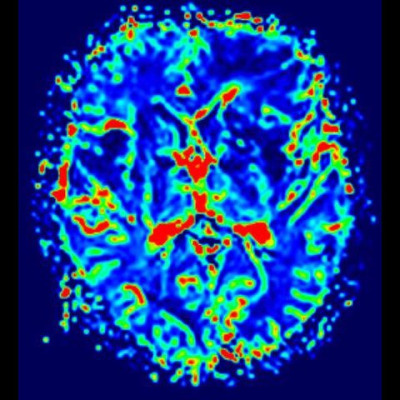

- (C) Difüzyon ağırlıklı görüntülerde sol frontaldeki kitle lezyonunda difüzyon kısıtlama bulgusu (oklar) mevcut olup perfüzyon MRG’de rCBV haritasında belirgin perfüzyon artışı izlenmemektedir (ok).

- Perfüzyon MRG’de düşük-orta düzey CBV değerleri izlenir. Lenfomalarda düşük CBV değerleri, kötü prognoz göstergesidir.